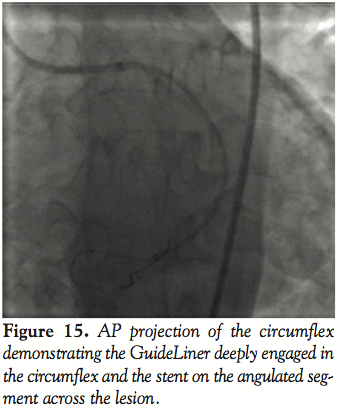

Case 1. A 63-year-old African American female presented with chest pain, bradycardia, and ECG evidence of a STEMI. The culprit vessel was the right coronary artery (RCA). The RCA was noted to have a complete occlusion at the bifurcation of the posterior descending artery (PDA) and posterolateral branches (Figure 1). The proximal RCA had a huge aneurysm measuring 1.0–1.2 cm with swirling of contrast in the aneurysmal segment and no visualization of the distal vessel even with injections of 20cc of contrast through an automated injection

system (ACIST CVi). PCI of the RCA was planned urgently. A 7 Fr JR4 (Medtronic) guiding catheter was used to engage the RCA. A 2 mm over the wire Sprinter balloon (Medtronic) was advanced into the distal RCA over a Prowater Flex 0.014 coronary guidewire (Abbott Vascular). The wire was unable to cross the occlusion and attempts to visualize the distal vessel were futile because of the proximal aneurysm and the swirling of contrast in the proximal RCA. At this point it was decided to place a GuideLiner catheter beyond the aneurysm in the distal RCA to facilitate subselective injection into the distal RCA. This was effectively achieved over the same wire (Figure 2). Once it was possible to see the distal vessel better, a hydrophilic 0.014-inch guidewire was advanced into the posterolateral and then the PDA respectively; PCI of both vessels was performed successfully using 24 mm Vision (Abbott Vascular) bare metal stents (Figure 3).

This case highlights another niche role of the GuideLiner catheter. In addition to providing support for facilitating stent delivery and enhanced backup for coronary interventions, this device allows safe subselective injections for better visualization of the distal vessel and decreasing contrast load. This particular application of the GuideLiner catheter has not been described in the literature thus far.

After guide catheter and wire placement, the GuideLiner catheter can be advanced over the wire through the hemostatic valve as an extension to the guide catheter for extra back up and deep guide engagement. The rest of the interventional procedure is completed as usual through the same hemostatic valve and guide catheter without need for disconnection and reattachment. The interventional equipment tracks over the wire and through the GuideLiner collar with exit at the distal tip of the catheter at the desired vascular location. On completion of the case, the GuideLiner catheter can be removed in a similar fashion to removal of a monorail balloon. In the first case, the use of the GuideLiner catheter as a tool for distal vessel visualization and subselective injection of contrast is showcased. This has never been described previously in the literature. Without the GuideLiner catheter, due to the presence of a coronary aneurysm the distal vessel was unable to be opacified. This was in spite of injecting 20 cc of contrast (10 cc/sec for 2 sec) via the ACIST CVi automatic injection system. Once advanced past the aneurysm, the GuideLiner allowed for subselective injection, providing complete distal vessel opacification utilizing <8 cc of contrast. This can be used to our advantage in coronary intervention on patients with compromised renal function minimizing contrast load and thereby potentially reducing the incidence of contrast associated nephropathy. This is especially important given the knowledge about adverse outcomes in patients with CIN following PCI.4 In this particular case, an unusual problem was elegantly solved with the assistance of the GuideLiner catheter.